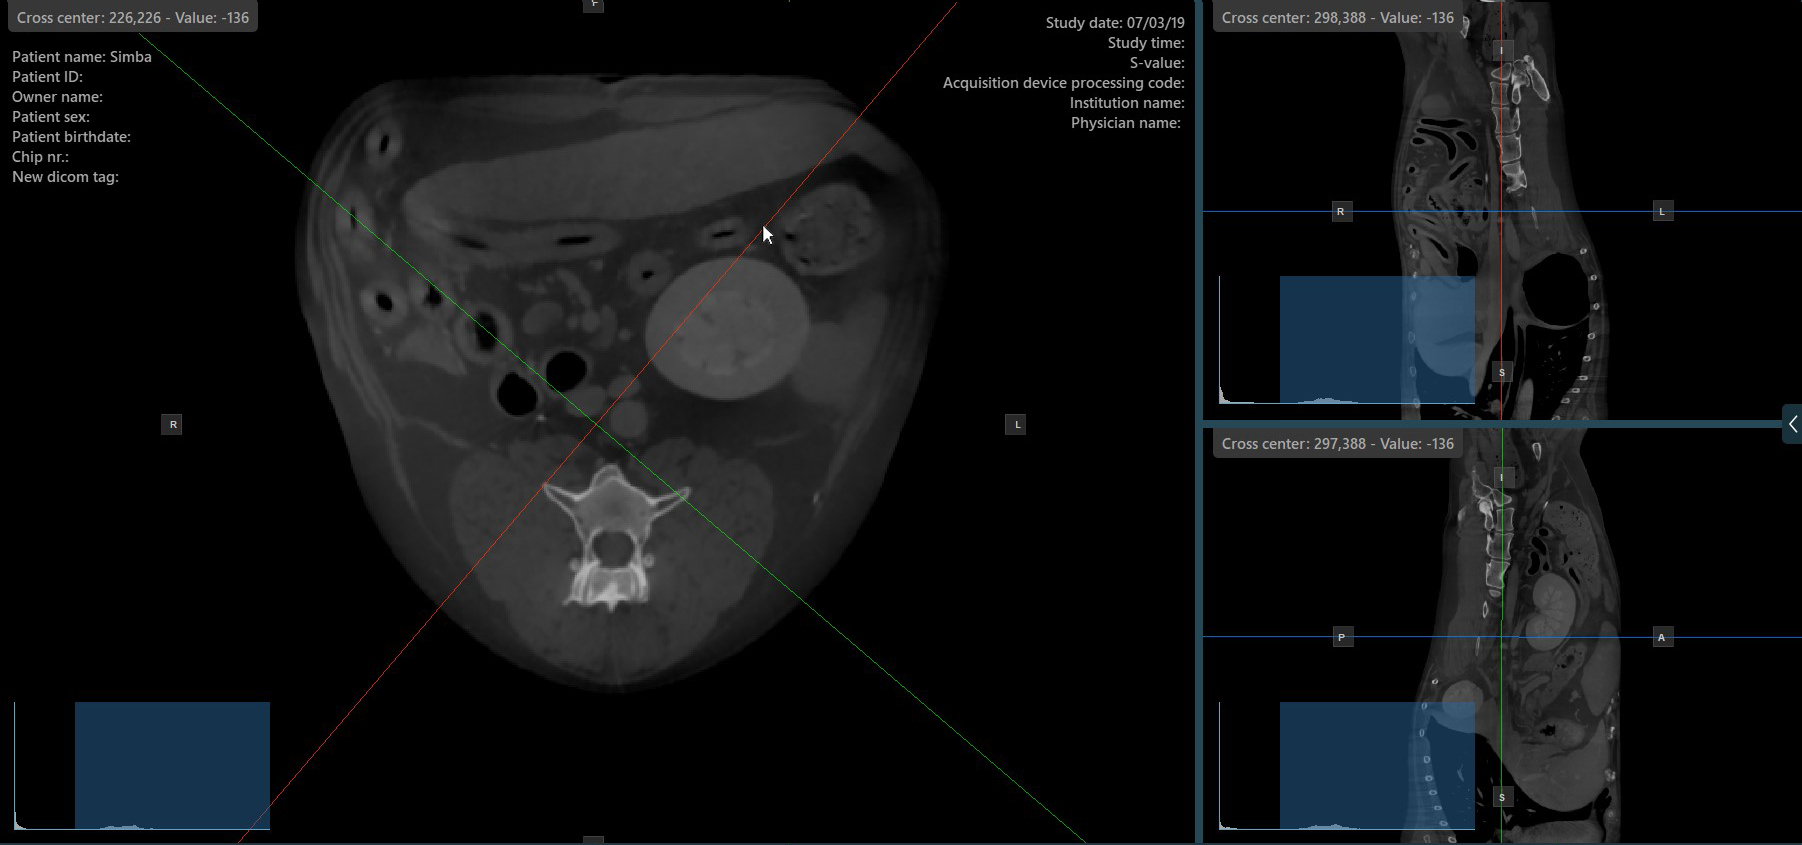

Change Slicer Rotation¶

Altering the rotation of a slicer will change the orientation of the corresponding image planes. Individual slicers can be selected by using the Select Item (Default) tool, assigned to the right mouse button by default.

Once the specific slicer is selected, drag the slicer in the desired direction to rotate it. The corresponding image plane’s orientation changes accordingly.

By default, each slicer can be rotated separately. The corresponding icon in the left toolbar of the CT Viewer will be deselected when the slicers are rotated individually.